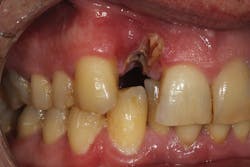

Although unpredictable, a greater amount of alveolar ridge loss following extraction usually occurs in the horizontal dimension and affects the buccal bone of the ridge.3 In fact, 50% of alveolar bone dimension can be lost after tooth extraction, with losses reported of up to 6–7 mm (figure 1). Two-thirds of this loss of bone volume can occur within the first three months of tooth extraction.4